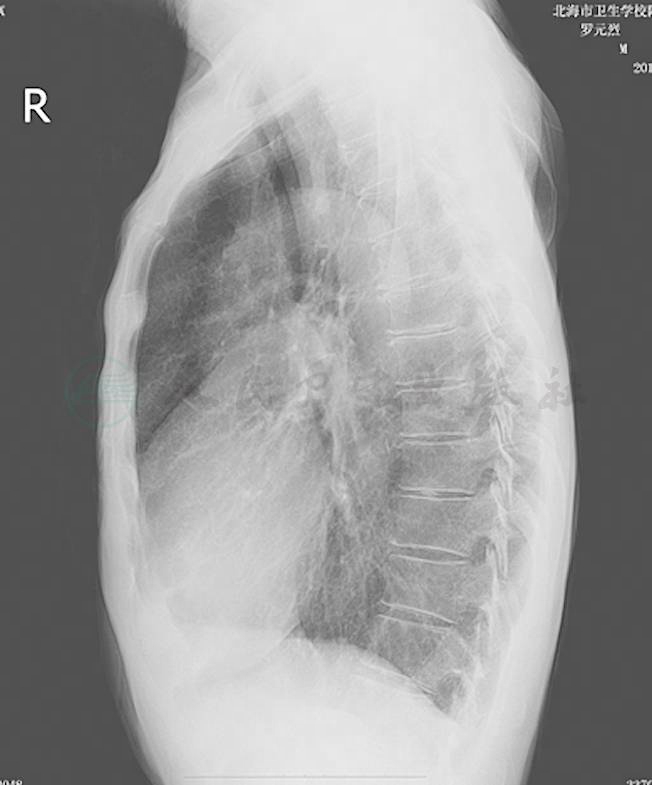

密度,肺野第二前肋间最高密度1.70 ± 0.05;肺门密度(背景均匀无骨骼重叠处)0.75 ± 0.05;肺周边部密度(近胸壁1cm处与单肋骨重叠处)0.65 ± 0.05;心影部密度(左心影内肺纹理处)0.40 ± 0.02;膈下部(肝肺重叠部)0.35 ± 0.02。对比度,肺野(最高密度)与肺门的对比度0.8 ± 0.15;气管(透亮区)与附近纵隔的对比度> 0.05;肺野(最高密度)与气管分叉下纵隔的对比度1.30 ± 15;肺野(最高密度)与邻近肋骨的对比度0.3 ± 0.10;锐利度,肋骨和锁骨骨棱,心脏与横膈边缘锐利;肺纹理边界清晰。颗粒性,肩胛骨下方软组织无颗粒状阴影,即无照片斑点影(图1~图4)。

图1  胸部后前位

图3  胸部后前位图像